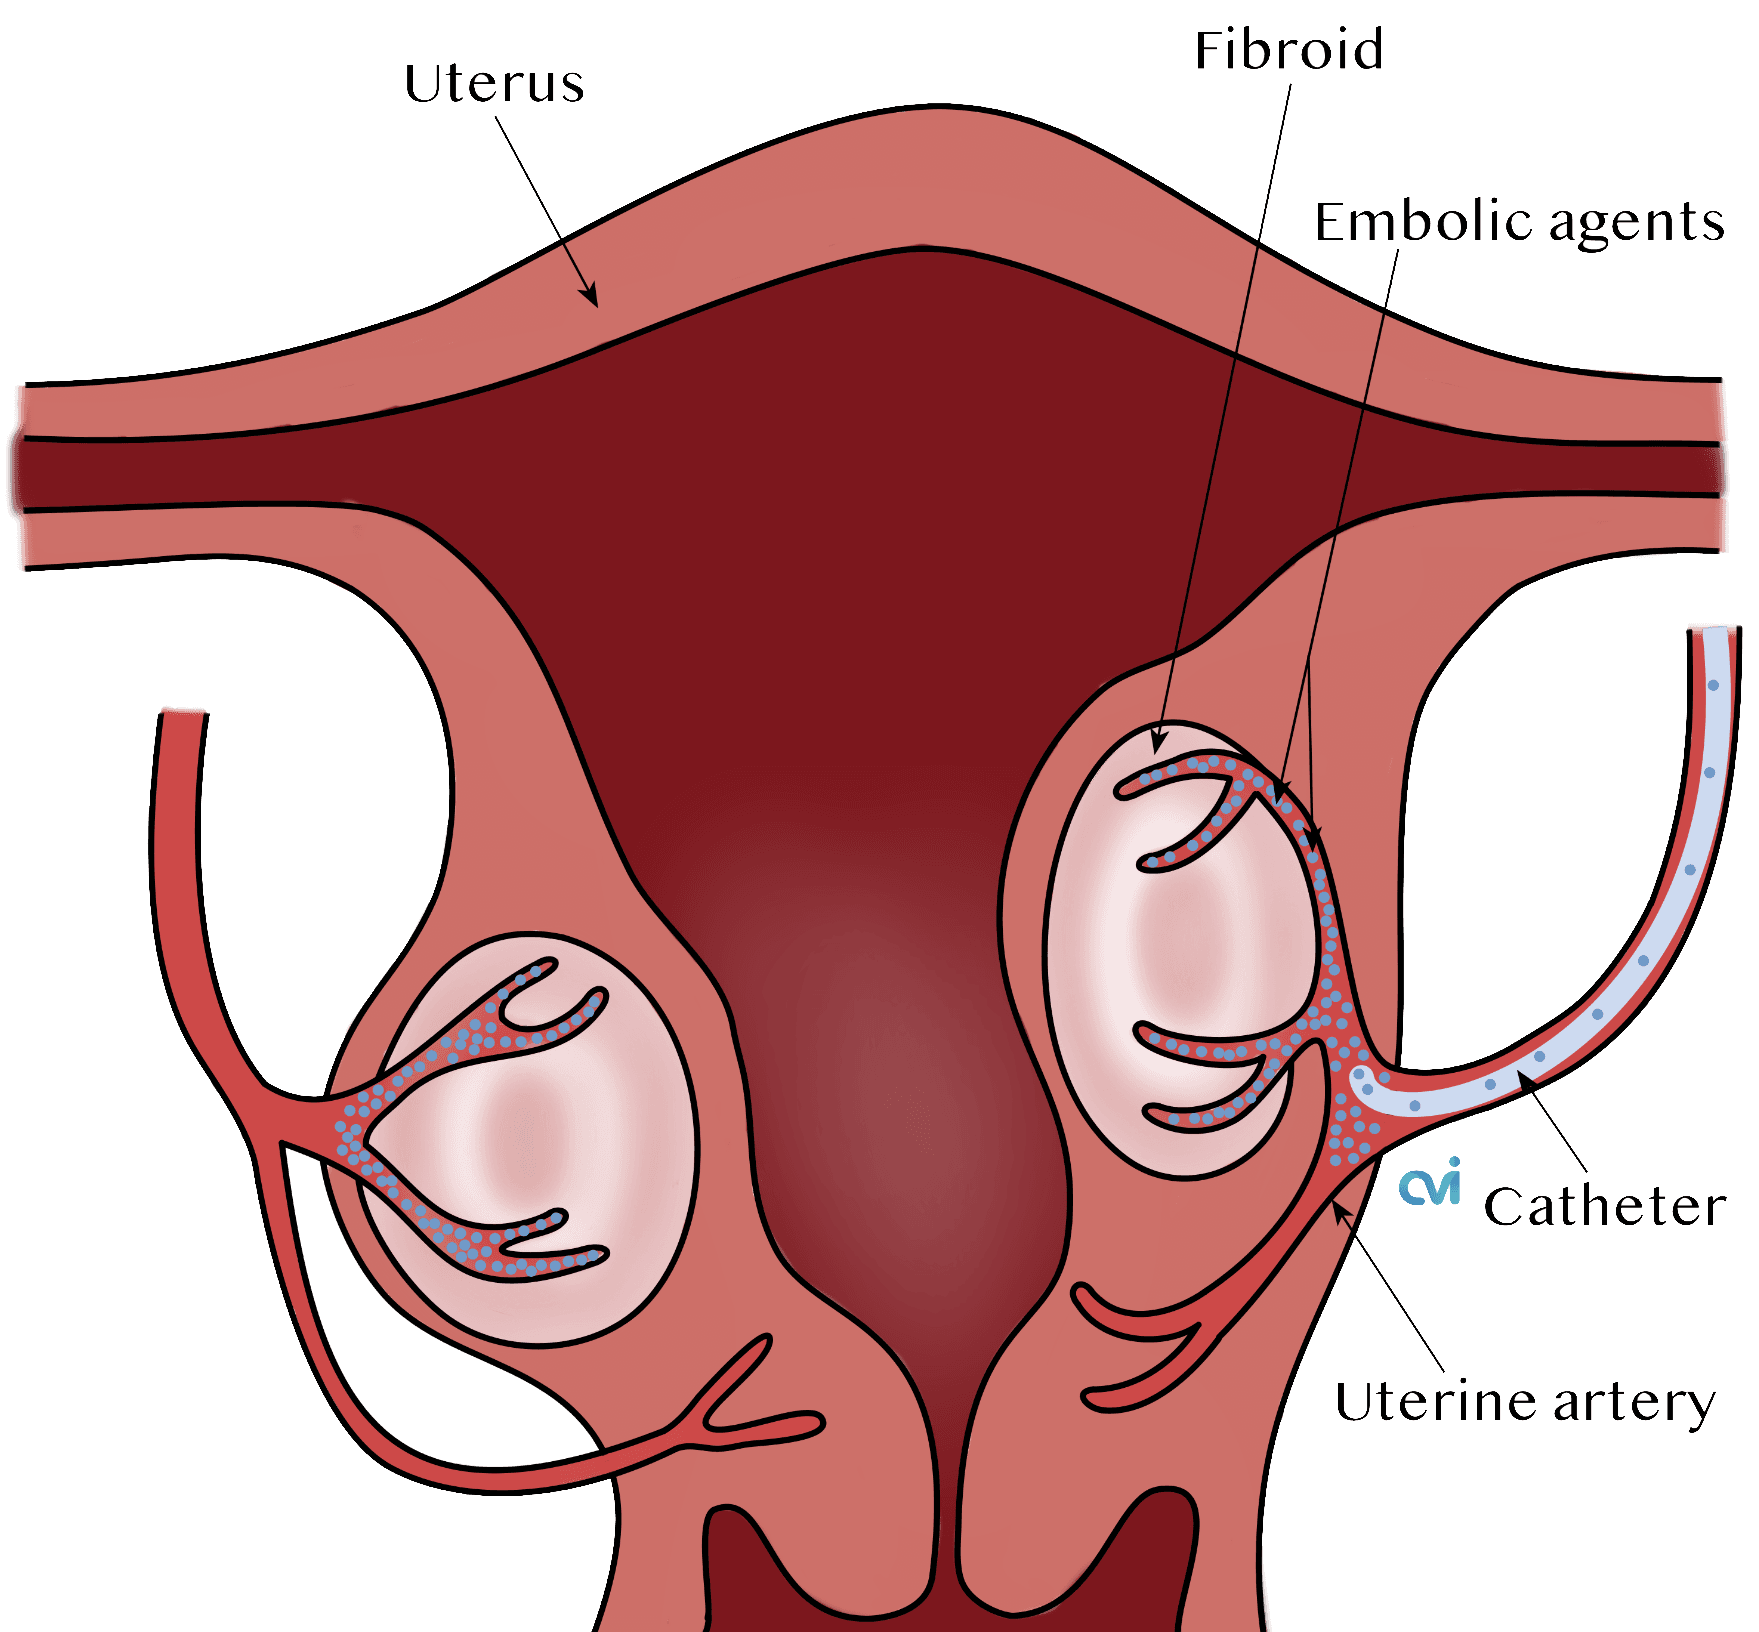

Fibroid embolization is an outpatient non-surgical procedure with minimal downtime. The procedure is done in an outpatient state of the art center where our interventional radiologist performs the fibroid treatment through a tiny tube called a catheter. This procedure can be performed by either placing the catheter in an artery at the top of the leg (called a femoral approach) or by placing it into an artery in the lower arm (called a radial approach). The two methods are illustrated below.

The patient is given a local and topical anesthetic to numb the skin and a mild sedative, so that the procedure is not painful. A sophisticated X-ray machine that creates moving pictures in “real” time enables the doctor to see the catheter as it is guided through the blood vessels and into the uterine artery.

The final step in fibroid embolization is the injection of tiny particles the size of sand particles through the catheter. The particles lodge in the blood vessels feeding the fibroids and cut off their blood supply, but the uterus and ovaries are spared.